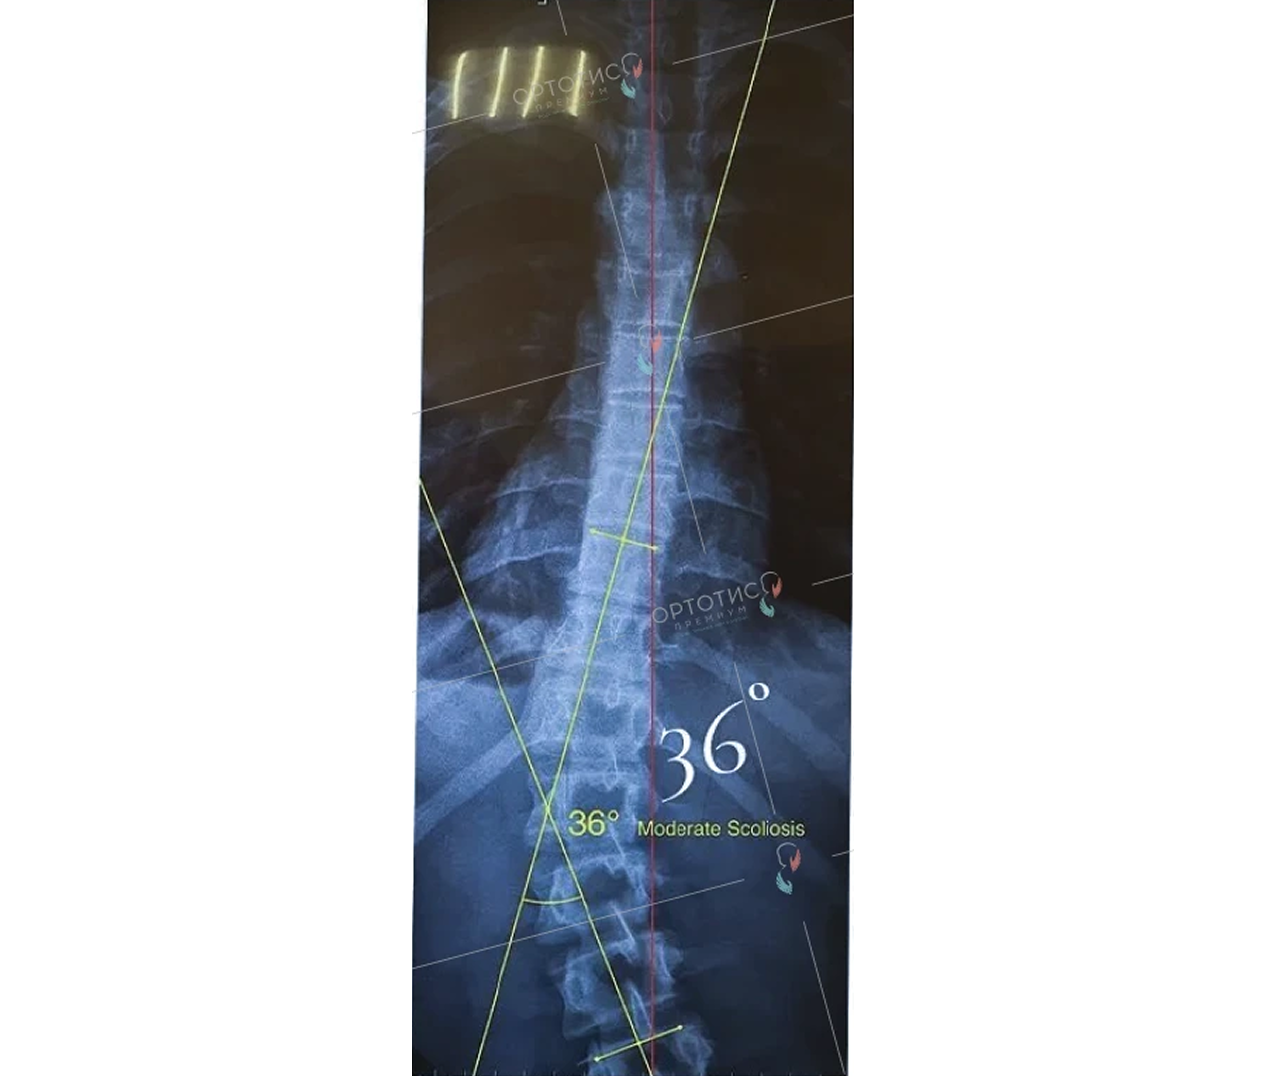

Корсет Шено в Алматы: эффективное лечение сколиоза

Корсет Шено — это «золотой стандарт» в лечении сколиоза у детей и подростков. В клинике Ортотис Центральная Азия в Алматы мы изготавливаем активные ортопедические корсеты, которые не просто удерживают позвоночник, а эффективно исправляют деформацию.

• Идиопатический сколиоз с углом искривления от 20° по Коббу;

• Быстро прогрессирующие формы деформации позвоночника;

• Кифосколиоз и другие нарушения осанки.

Мы используем высокоточное 3D-моделирование, что позволяет создать корсет, идеально соответствующий анатомии ребенка. Это обеспечивает максимальную коррекцию при сохранении мобильности. Наши техники-ортопеды в Алматы проводят регулярную коррекцию изделия по мере исправления позвоночника.